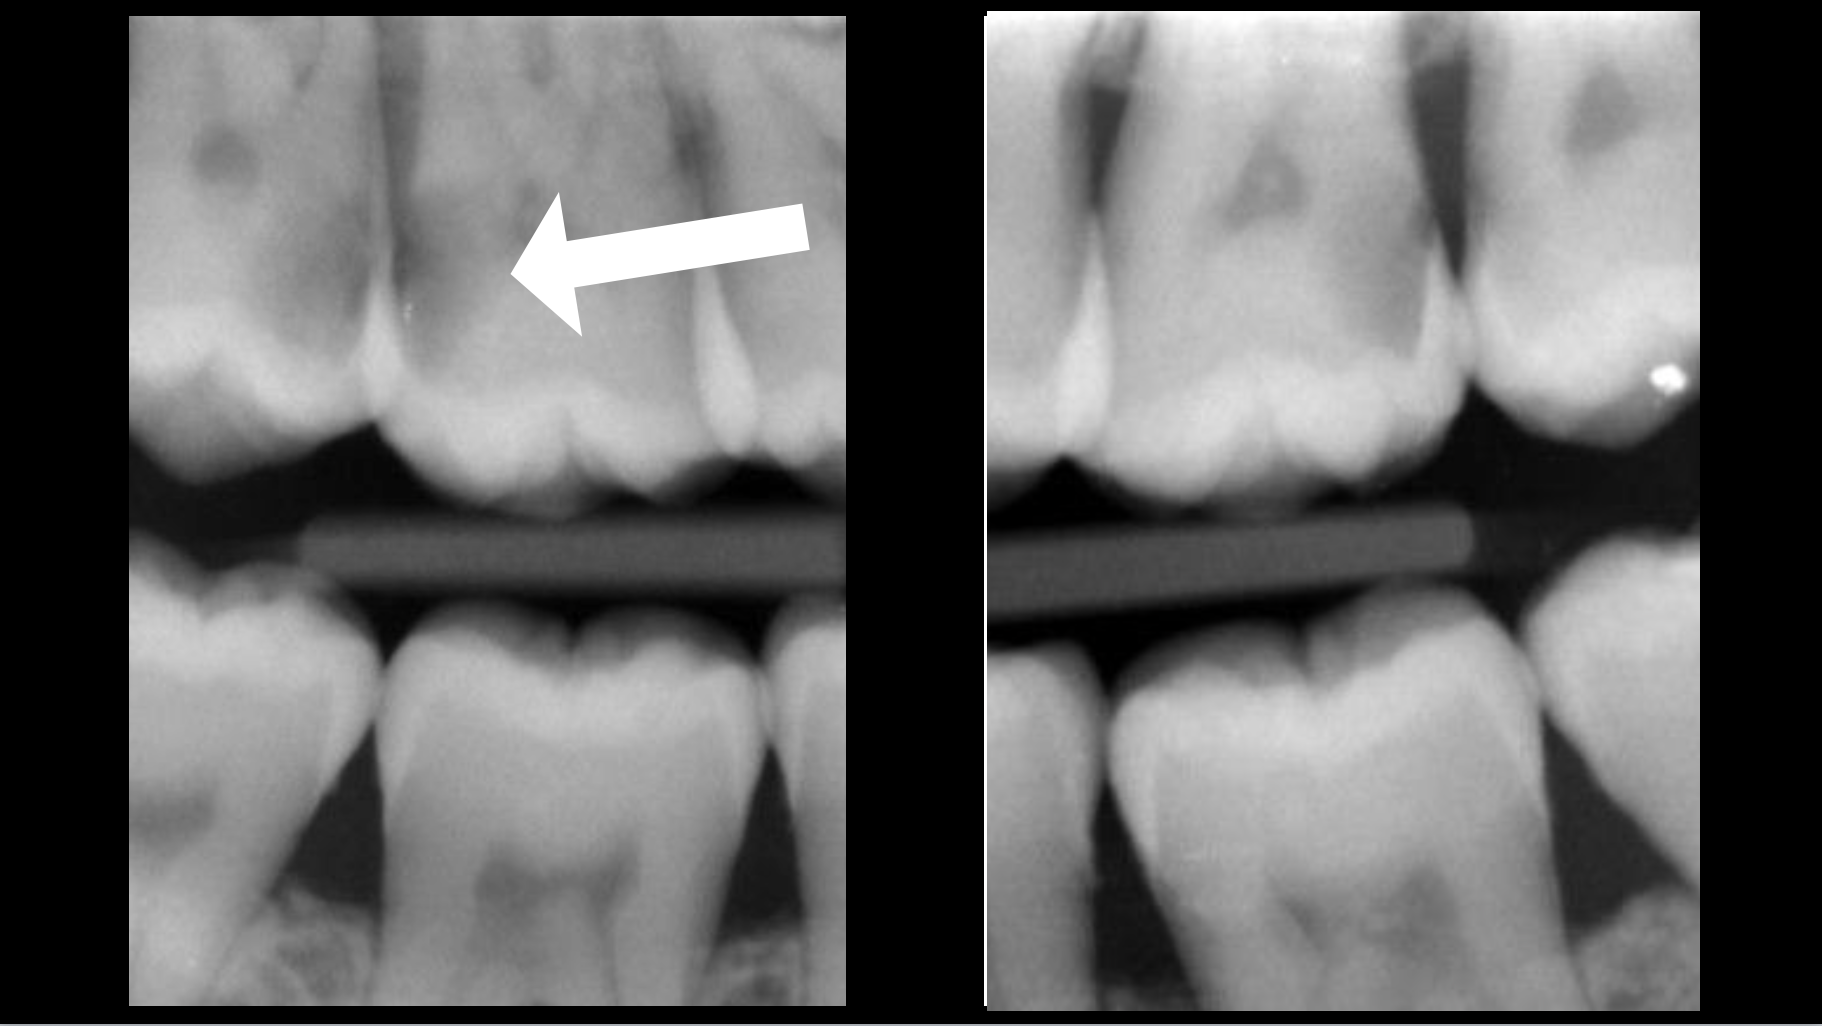

Cette nécrose pulpaire peut, si l’endodonte est infecté, avoir causé une réaction inflammatoire osseuse, c’est la lésion apicale :

En l’absence de lésion apicale, le traitement canalaire a pour objectif de maintenir la bonne santé osseuse péri apicale.

En présence d’une lésion apicale, le traitement canalaire a pour objectif de permettre la cicatrisation osseuse péri apicale.

Cas clinique

Traitement canalaire : 80-95% de taux de succès

- Une infection intra-canalaire est présente malgré le traitement canalaire déjà en place, et provoque une lésion apicale.

Cas clinique

Retraitement canalaire : 80-95% de taux de succès